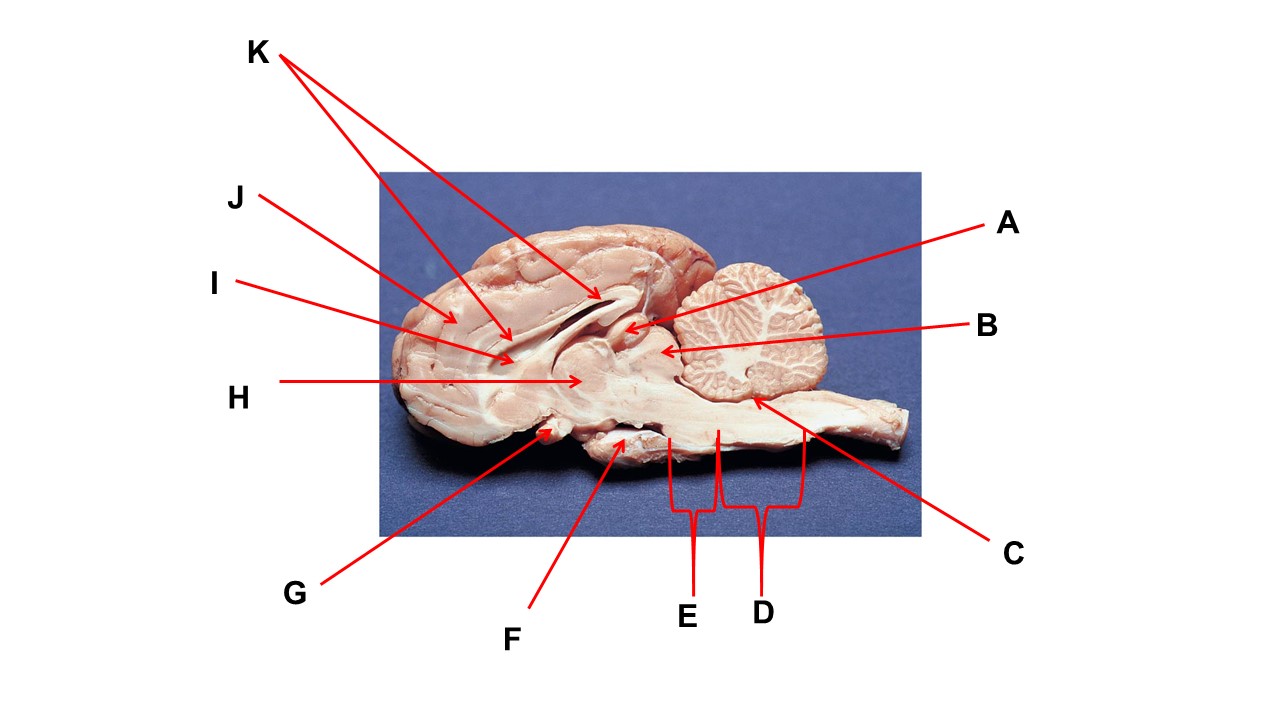

Name the structure at the tip of arrow A.

pineal gland

The cavity at the tip of arrow I is the _____.

lateral ventricular

The cavity at the tip of arrow I is filled with ______.

cerebrospinal fluid

Name the structure at the tip of arrow F

mammillary body

Name the structure at the tip of arrow A.

pineal gland

Name the structure at the tip of arrow G

optic chiasma

Name the nerve at the tip of arrow H.

optic